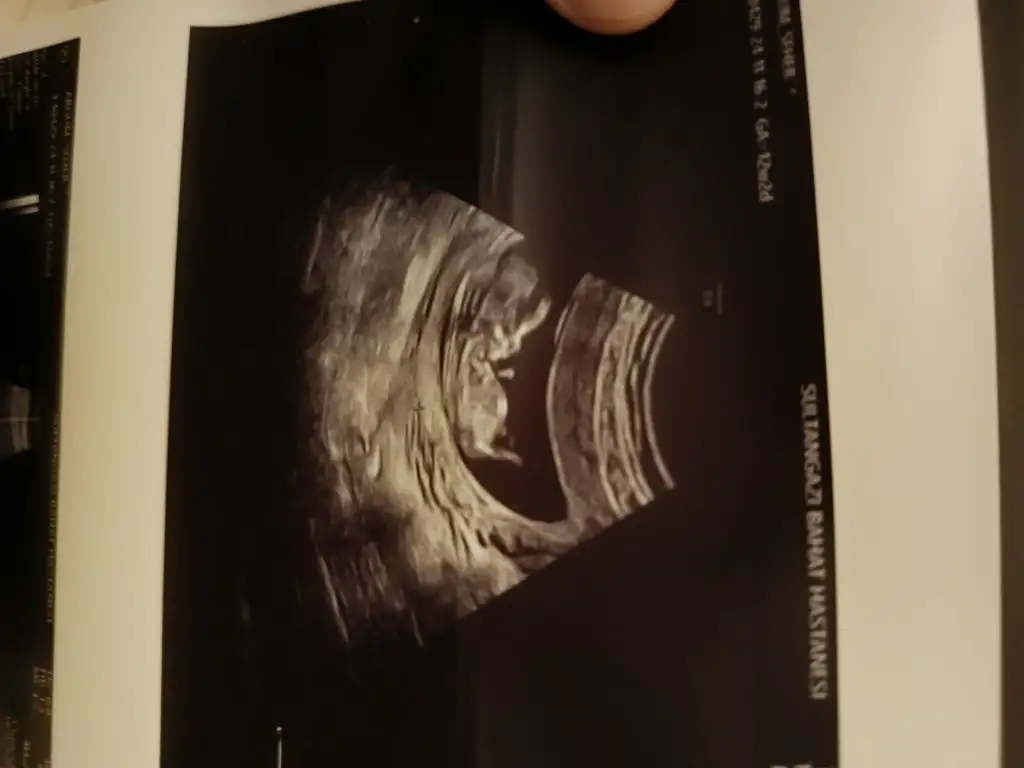

Cinsiyet tahmininde bulunur musunuz kızlar 12 haftalık burda

Eklentiler

• IMG20241119205255.webp

13,8 KB · Görüntüleme: 568